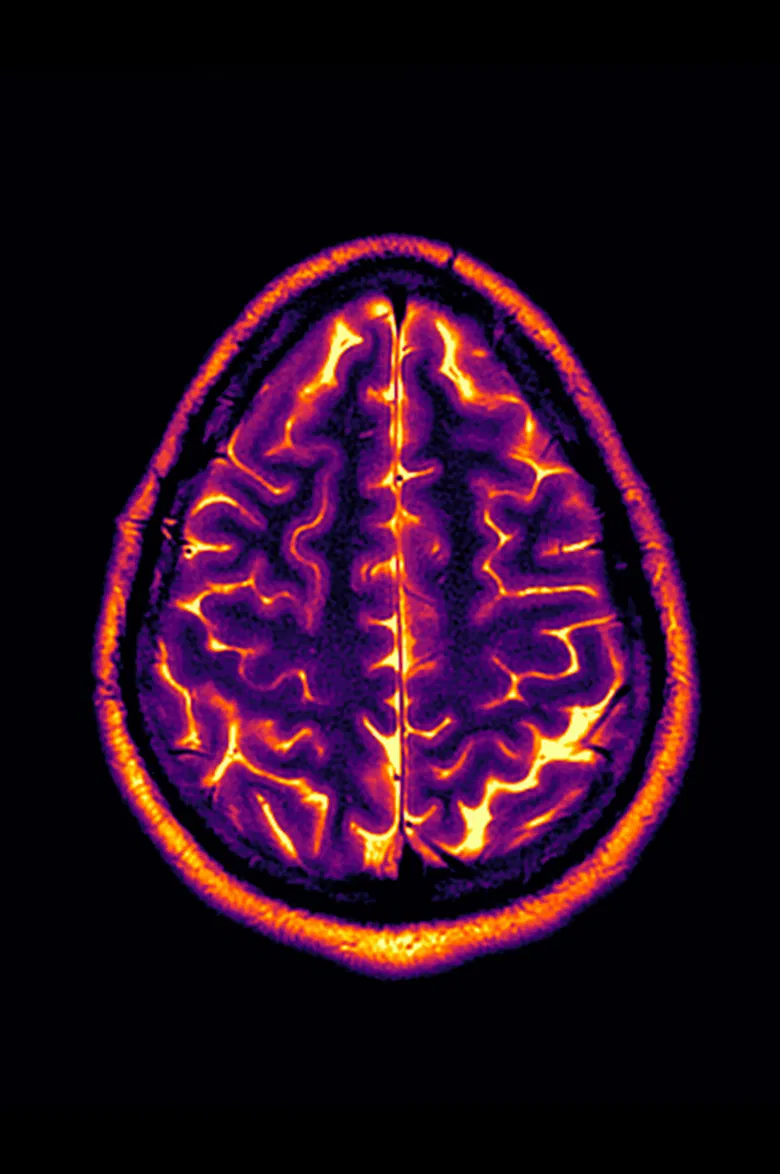

Living with a progressive disease like multiple sclerosis means annual tests and doctor’s visits, and with that comes the usual anxiety about whether this will be the year. Conclusion: Stable Disease is an experimental video made from the artist’s personal MRI image scans from 2018-2022